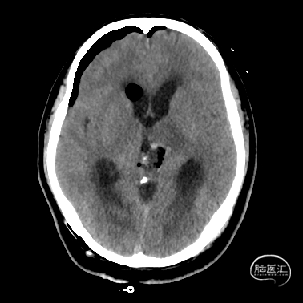

术后当天CT

术后1周CT复查